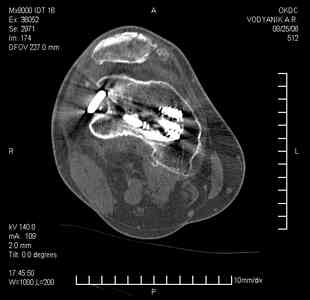

Уважаемые коллеги,В ортопедическое отделение обратился пациент: мужчина 47 лет, который в течение 4-х лет дваждыполучил травму костей, образующих правый коленный сустав. В 2002 v внутрисуставной оскольчатыйперелом проксимального метаэпифиза правой большеберцовой кости; в 2005 v внутрисуставнойоскольчатый перелом дистального метаэпифиза правой бедренной кости. В обоих случаях в разных лечебных учреждениях проводилось оперативное лечение переломов.При осмотре в отделении на основании результатов клинического осмотра и данных визуальныхметодов обследования поставлен диагноз:тугой ложный сустав дистальной трети правой бедренной кости, состояние после накостногоостеосинтеза перелома типа 33-В2.2 ; несросшийся перелом надколенника; неправильно сросшийсяперелом латерального мыщелка правой большеберцовой кости, состояние после металлоостеосинтезаперелома 41-В2.2; сочетанная осевая деформация правой ноги: варусная деформация правого бедра,вальгусная деформация правой голени; посттравматический артроз коленного сустава 4 ст по Kellgren-Lowrence; выраженное нарушение функции ходьбы и опоры. Внешний вид ноги больного, данные рентгенографического обследования и избирательно выделенные компьютерные томограммы приведены в приложении. В именах КТ использовано кодирование уровня по АО, т.е. _41, например, означает проксимальную треть голени.В отделении намечен v очень предварительно v следующий план лечения: 1. Иметь ввиду перспективу тотального эндопротезирования коленного сустава. 2. С учетом п.1 при проведении действий, направленных на устранение ложного сустава бедренной кости не использовать материалы, не подвергающиеся трансформации. 3. В ходе операции, направленной на устранение ложного сустава: А. удалить все металлоконструкции; Б. ревизовать зону пролежня под пластиной на бедре, при наличии признаков достаточной жизнеспособности кости выполнить остеопериостальную декортикацию, дрилинг ложа пластины; В. Удалить рубцовую ткань по плоскости ложного сустава, и в пространстве между костными форагментами, насечь обращенные друг к другу поверхности. Ввести штифт с блокированием (например Stryker с учетом особенностей расположения дистальных блокирующих винтов у этойконструкции). Осуществить остеосинтез с учтанением варусной деформации бедренной кости. Пространство в зоне ложного сустава и пустоты в метафизе бедренной кости заполнить резорбирующимся цементом на основе гидроксиапатита кальция. Для дистальной фиксации использовать винты с переменным шагом резьбы. Вариант:, винты вводить после заполнения метафиза цементом. Дополнительные виды создания межфрагментарной компрессии во встречно-боковом направлении обсуждаются. Г. Быть готовым к кровопотере. Д. Учесть высокий риск инфекции, тромбоэмболических осложнений. Е. Вопрос о внешней иммобилизации решить по результатам оценки стабильности остеосинтеза. Вариант - одноосевой стержневой аппарат для шунтирования гвоздя с модулем на голени и дистракцией коленного сустава в течение 3-5 недель. Просим вашей критики намеченного плана и конструктивных предложений. С уважением к сообществу, Ординатор В.С. Саплин

Движения приличные, есть за что бороться. Такая ротация голени кнаружи, если она действительно есть (для уточнения можно сделать КТ на уровне обоих метафизов и бедреных, и берцовых ксотей, не меняя положение ног во время съемки), большого значения не имеет. А уж на фоне всего остального тут - вообще говорить не о чем.